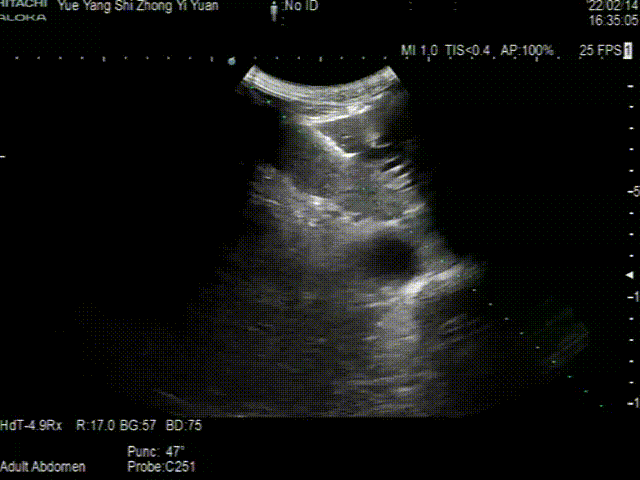

穿刺前,超声医学科主任吴松梅在彩超下仔细扫查患者肝内胆管及毗邻血管,分析超声实时图像,选择最佳穿刺点和穿刺路径,在彩超引导下穿刺针精准地穿刺入患者扩张的左肝内胆管,不到1分钟就用注射器抽吸见白色胆汁。手术过程顺利,患者无任何不适,术后第一天随访,患者明显好转。

▲介入穿刺针精准插入左肝胆管内、送入导丝